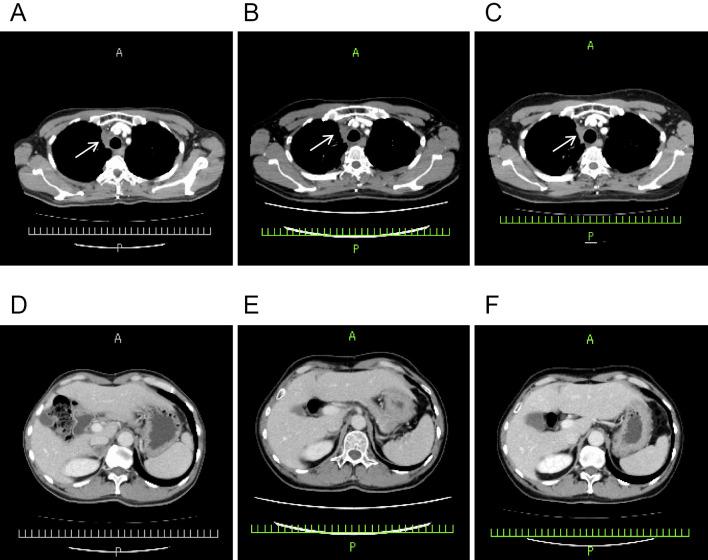

A 51-year-old man underwent second-line treatment for non-small-cell lung cancer (NSCLC) with the immune checkpoint inhibitor (ICI) pembrolizumab. On day 2 after two cycles of pembrolizumab, he presented with edema limited to the left third, fourth, and fifth fingers. Based on symptoms, laboratory results, and contrast-enhanced magnetic resonance imaging (MRI) findings, we diagnosed him with tenosynovitis. We prescribed oral prednisolone (0.5 mg/kg/day), and pembrolizumab was continued. Prednisolone immediately relieved the symptoms, and the tumor was still shrinking on day 21 after eight cycles of pembrolizumab. ICI-induced tenosynovitis was managed while continuing ICI usage, suggesting that 0.5 mg/kg/day prednisone might be effective for tenosynovitis without ICI cessation.

一名51岁男性接受了免疫检查点抑制剂(ICI)帕博利珠单抗用于非小细胞肺癌(NSCLC)的二线治疗。在接受两个周期帕博利珠单抗治疗后的第2天,他出现了仅局限于左手第三、第四和第五指的水肿。根据症状、实验室检查结果以及对比增强磁共振成像(MRI)结果,我们诊断他患有腱鞘炎。我们开具了口服泼尼松龙(0.5 mg/kg/天),并继续使用帕博利珠单抗。泼尼松龙立即缓解了症状,在接受八个周期帕博利珠单抗治疗后的第21天,肿瘤仍在缩小。在继续使用ICI的同时对ICI诱导的腱鞘炎进行了处理,这表明0.5 mg/kg/天的泼尼松可能对腱鞘炎有效且无需停用ICI。